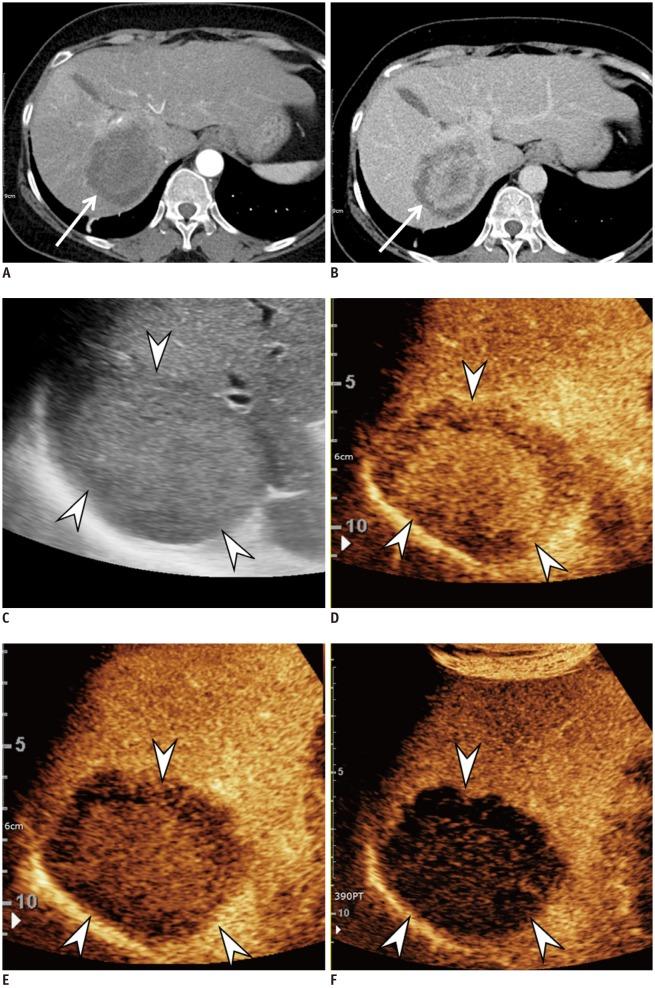

Hepatocellular carcinoma (HCC) can be noninvasively diagnosed on the basis of its characteristic imaging findings of arterial phase enhancement and portal/delayed "washout" on computed tomography (CT) and magnetic resonance imaging (MRI) in cirrhotic patients. However, different specific diagnostic criteria have been proposed by several countries and major academic societies. In 2018, major guideline updates were proposed by the Association for the Study of Liver Diseases, European Association for the Study of the Liver (EASL), Korean Liver Cancer Association and National Cancer Center (KLCA-NCC) of Korea. In addition to dynamic CT and MRI using extracellular contrast media, these new guidelines now include magnetic resonance imaging (MRI) using hepatobiliary contrast media as the first-line diagnostic test, while the KLCA-NCC and EASL guidelines also include contrast-enhanced ultrasound (CEUS) as the second-line diagnostic test. Therefore, hepatobiliary MR contrast media and CEUS will be increasingly used for the noninvasive diagnosis and staging of HCC. In this review, we discuss the emerging role of hepatobiliary phase MRI and CEUS for the diagnosis of HCC and also review the changes in the HCC diagnostic criteria in major guidelines, including the KLCA-NCC practice guidelines version 2018. In addition, we aimed to pay particular attention to some remaining issues in the noninvasive diagnosis of HCC.

肝细胞癌 (HCC) 在肝硬化患者的计算机断层扫描 (CT) 和磁共振成像 (MRI) 上具有动脉期增强和门静脉/延迟“洗脱”的特征性影像学表现,可以进行无创诊断。然而,不同的国家和主要学术协会提出了不同的具体诊断标准。2018 年,肝病研究协会、欧洲肝病研究协会 (EASL)、韩国肝癌协会和韩国国家癌症中心 (KLCA-NCC) 提出了主要指南更新。除了使用细胞外对比剂的动态 CT 和 MRI 外,这些新指南现在还包括使用肝胆对比剂的磁共振成像 (MRI) 作为一线诊断测试,而 KLCA-NCC 和 EASL 指南还包括对比增强超声 (CEUS) 作为二线诊断测试。因此,肝胆磁共振对比剂和 CEUS 将越来越多地用于 HCC 的无创诊断和分期。在这篇综述中,我们讨论了肝胆期 MRI 和 CEUS 在 HCC 诊断中的新作用,并回顾了主要指南中 HCC 诊断标准的变化,包括 2018 年 KLCA-NCC 实践指南。此外,我们特别关注 HCC 无创诊断中仍存在的一些问题。